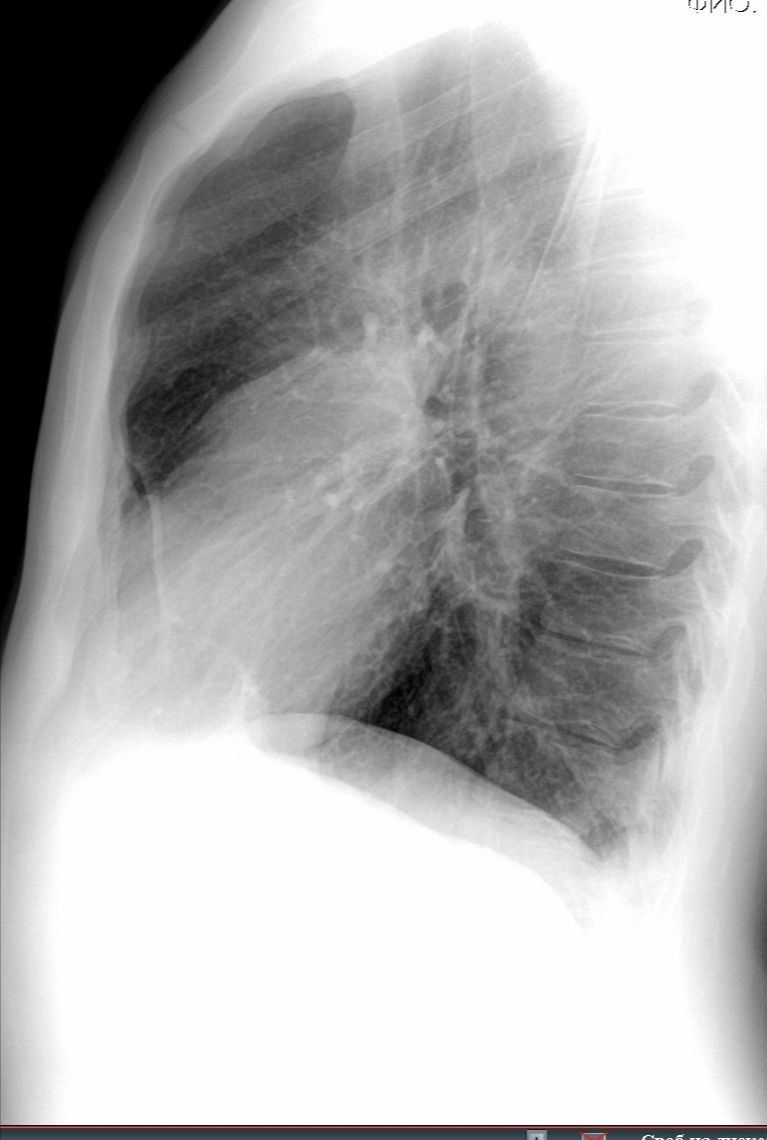

Здравствуйте, пациент 1984 г. р. Проф осмотр. Слева пневмоторакс?

источник

Да